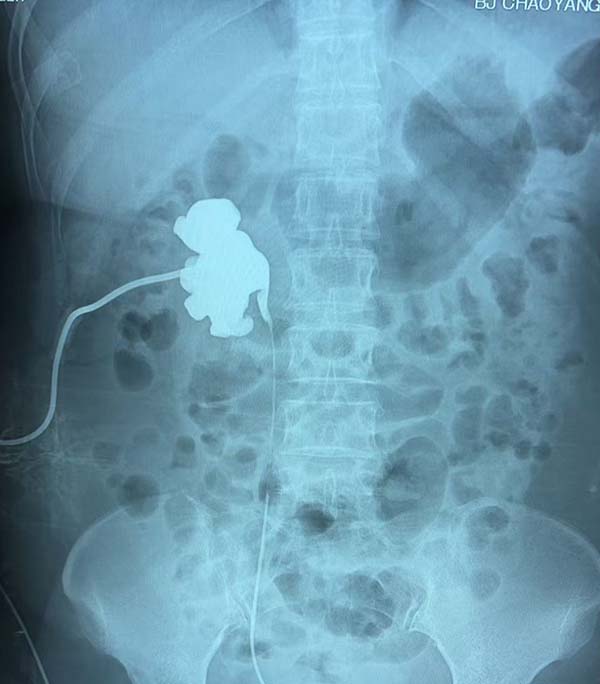

术后患者造影图显